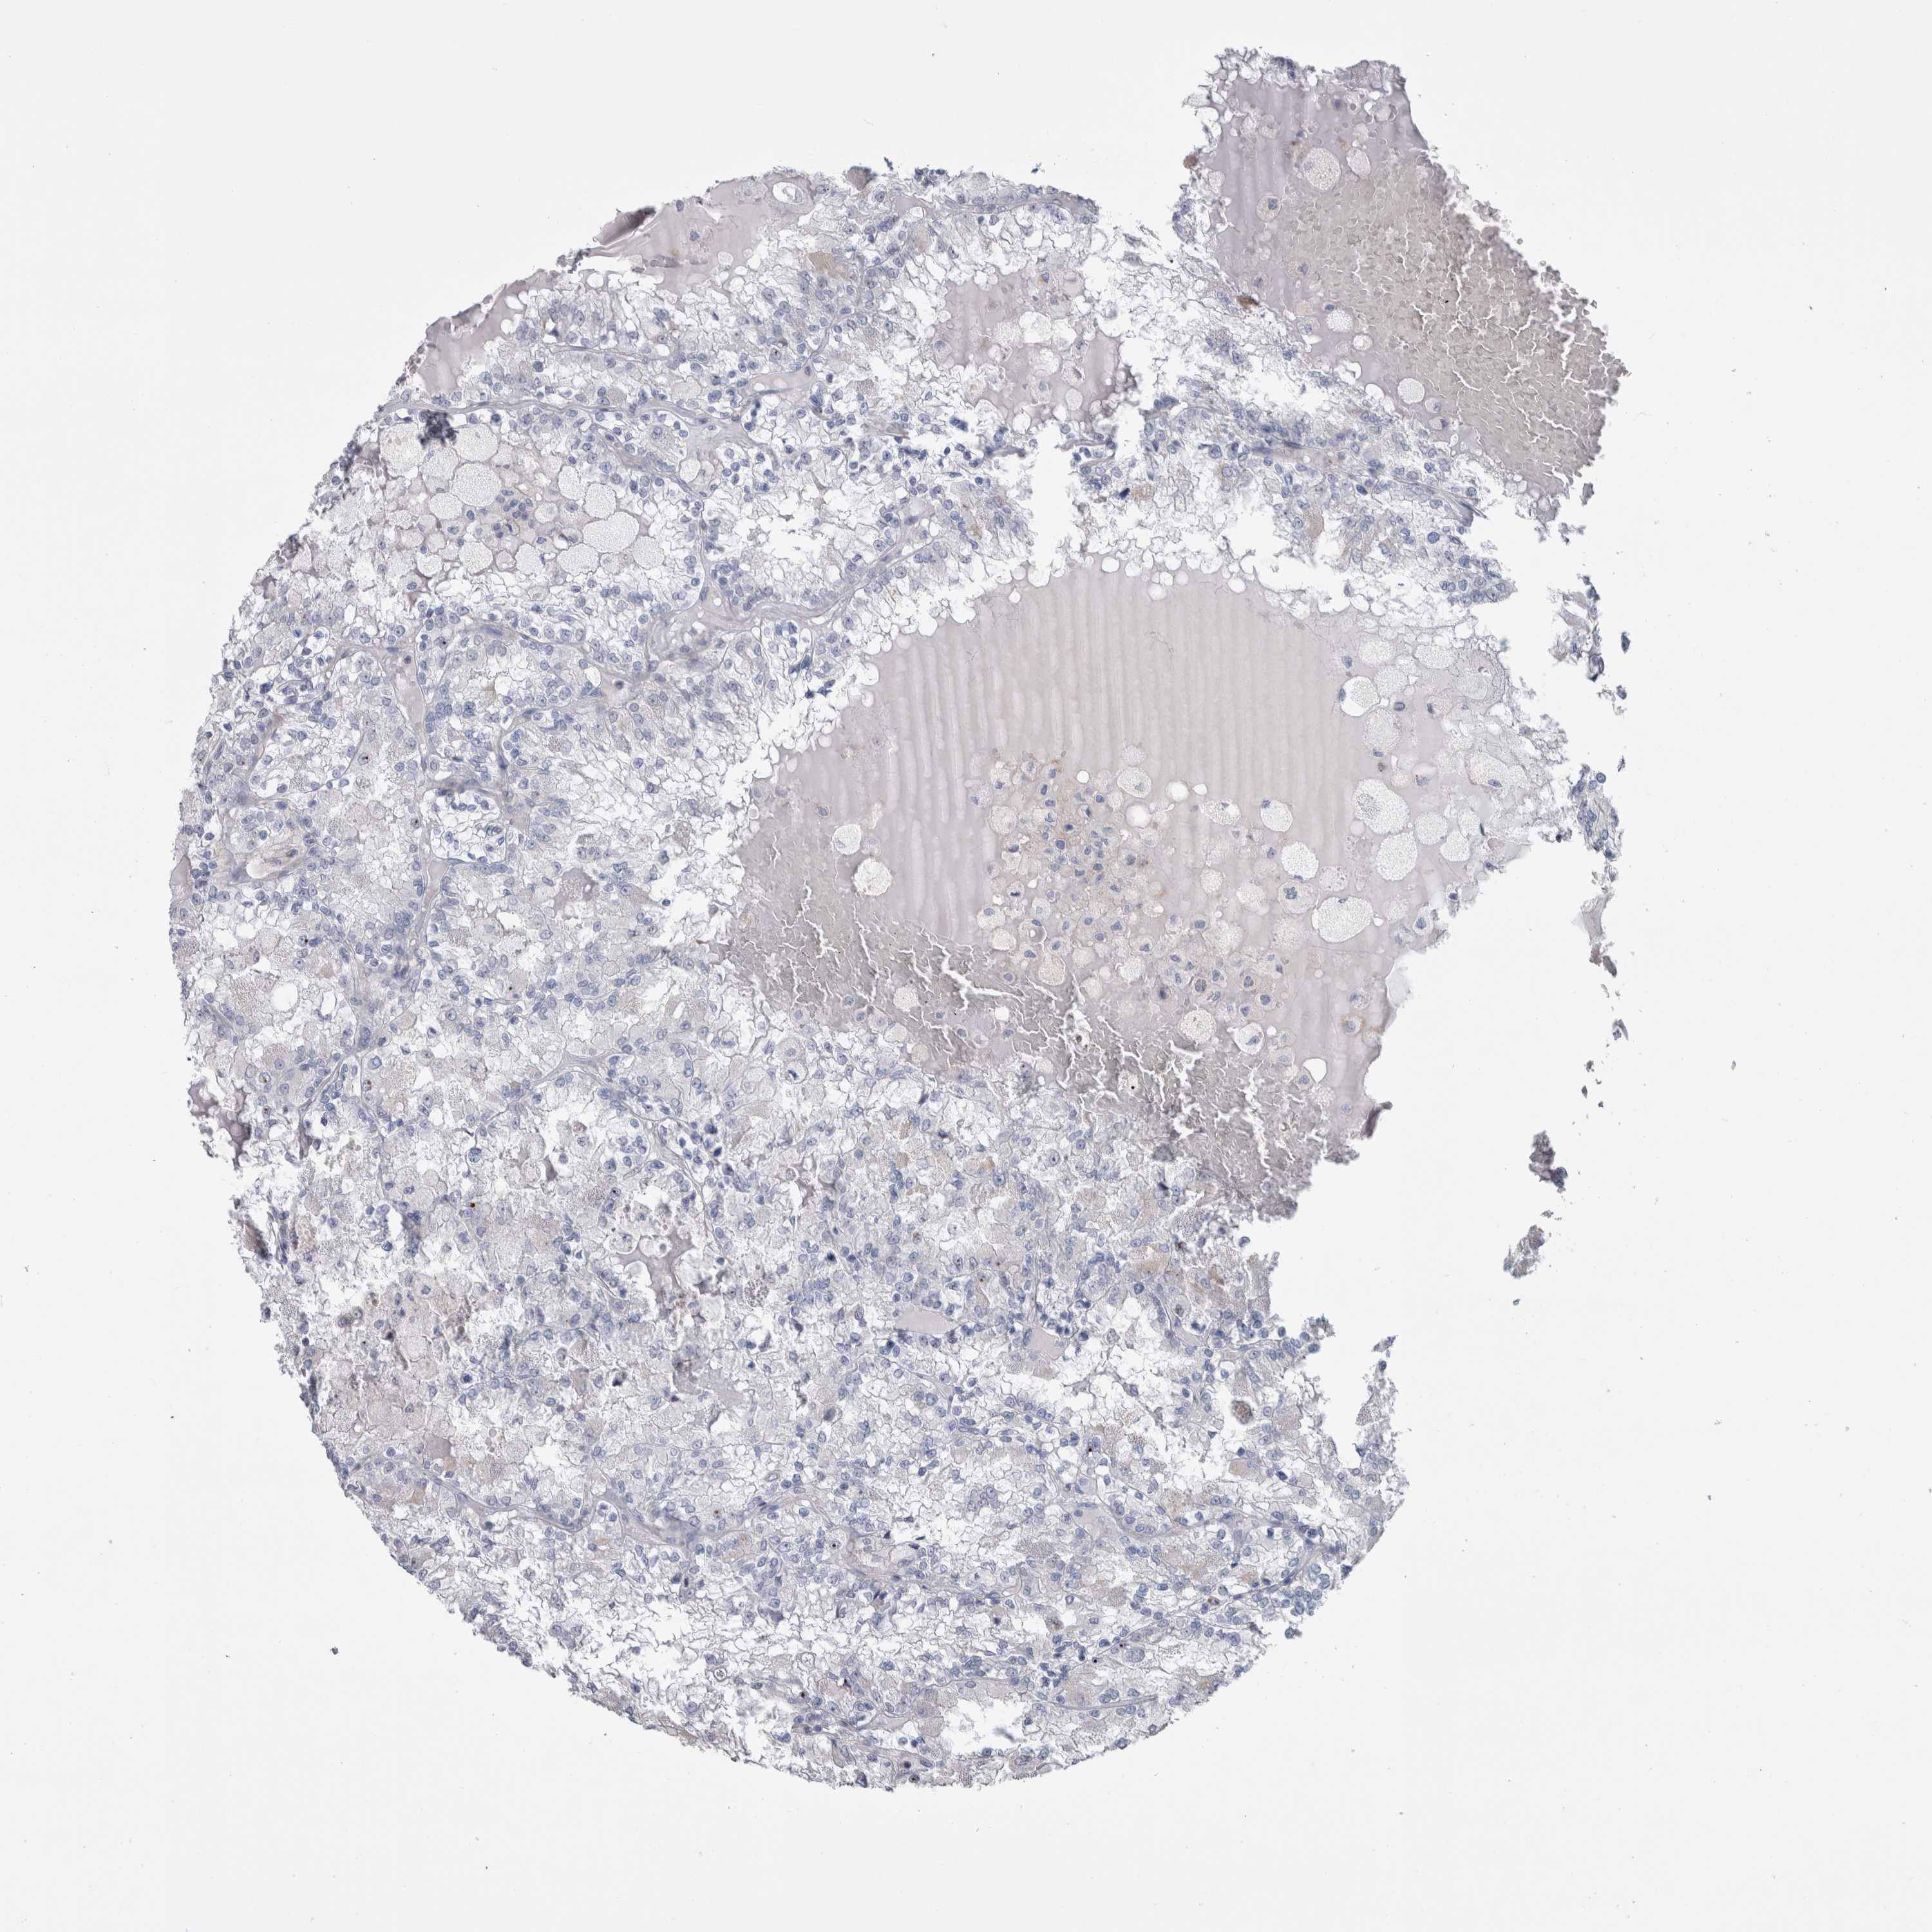

KIDNEY RENAL PAPILLARY CELL CARCINOMA (TCGA) - Interactive survival scatter ploti

The Survival Scatter plot shows the clinical status (i.e. dead or alive) for all individuals in the patient cohort, based on the same data that underlies the corresponding Kaplan-Meier plots. Patients that are alive at last time for follow-up are shown in blue and patients who have died during the study are shown in red.

The x-axis shows the expression levels (FPKM) of the investigated gene in the tumor tissue at the time of diagnosis. The y-axis shows the follow-up time after diagnosis (years). Both axes are complimented with kernel density curves demonstrating the data density over the axes. The top density plot shows the expression levels (FPKM) distribution among dead (red) and alive patients (blue). The right density plot shows the data density of the survived years of dead patients with high and low expression levels respectively, stratified using the cutoff indicated by the vertical dashed line through the Survival Scatter plot. This cutoff is automatically defined based on the FPKM cutoff that minimizes the p-score. The cutoff can be changed by dragging the vertical line or by entering a cutoff value in the square labeled "Current cut-off".

Under the Survival Scatter plot the p-score landscape (black curve; left axis) is shown together with dead median separation (red curve; right axis). Dead median separation is the difference in median mRNA expression between patients who have died with high and low expression, respectively. It is calculated as follows: median FPKM expression of dead patients with high expression - median FPKM expression of dead patients with low expression. This is intended to aid the user in visually exploring custom cutoffs and the associated p-scores and dead median separation.

Individual patient data is displayed and can be filtered by clicking on one or more of the category buttons on the top of the page. Categories describing expression level and patient information include: high, low, alive, dead, female, male and tumor stages. The scale of the x-axis can be toggled between linear and log-scale by clicking on the "x log" button. Mouse-over function shows TCGA ID, patient information and mRNA expression (FPKM) for each patient.

& Survival analysisi

Kaplan-Meier plots summarize results from analysis of correlation between mRNA expression level and patient survival. Patients were divided based on level of expression into one of the two groups "low" (under cut off) or "high" (over cut off). X-axis shows time for survival (years) and y-axis shows the probability of survival, where 1.0 corresponds to 100 percent.

IL33 is potential prognostic, high expression is unfavorable in Kidney Renal Papillary Cell Carcinoma (TCGA)

Best expression cut offi

Based on the FPKM value of each gene, patients were classified into two groups and association between prognosis (survival) and gene expression (FPKM) was examined. The best expression cut-off refers the FPKM value that yields maximal difference with regard to survival between the two groups at the lowest log-rank P-value. Best expression cut-off was selected based on survival analysis .